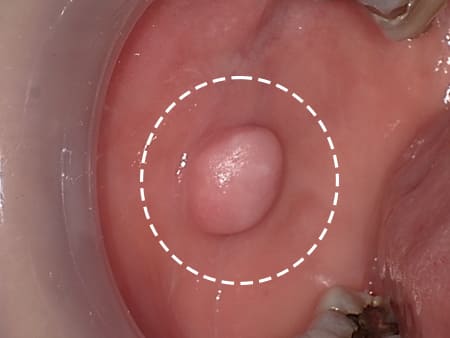

症例2 頬粘膜線維腫(40歳代 女性)

数年前から気になっていた頬粘膜のできものが徐々に大きくなり、よく噛むようになり来院されました。粘膜組織に弾性硬の腫瘍を突出を認め、頬粘膜良性腫瘍と診断し、摘出術を施行しました。